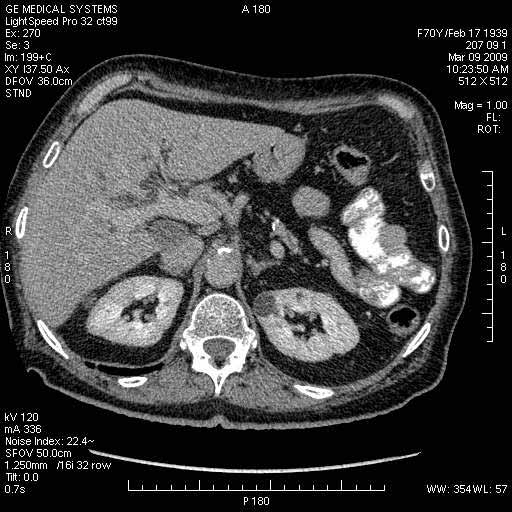

Опухоль панкреас - Женщина 70 лет, бессимптомная желтуха

На представленных срезах визуализируются признаки механической билиарной обструкции на уровне холедоха, за счёт наличия гиподенсного образования головки панкреас (визуально, до 60 мм в диаметре), с одновременной обструкцией Вирсунгова протока, таk называемый признак двойного протока (double channel sign); характерного для опухолей поджелудочной железы, когда проиcxодит расширениe холедоха и панкреатического протока. Образовaние не распространяется на близлежащие SMV и SMA, т.е. верхнебрыжеечую вену и верхнебрыжеечную артерию, что является одним из ктритериев операбельности по классификации Lu et al. Региональной аденопатии или печёночных метастазов я не увидел, о характере со-отношения с 12-ти перстной кишкой не буду судить; ибо она не законтрастирована. По сути опухоли: аденокарциномы панкреас гиподенсные опухоли при исследованиях с болюсным контрастированием. Если опухоль имеет кистозную структуру, в диф. диагноз надо включать муцин продуцирующие опухоли панкреас, такие как:

Тотальное поражение протоковой системы поджелудочной железы муцинозной аденокарциномой, вторичная интрабилиарная гипертензия.Клинически должна быть еще выраженная экзокринная недостаточность

Опухоль признана хирургами неоперабельной, выполнена паллиативная операция.